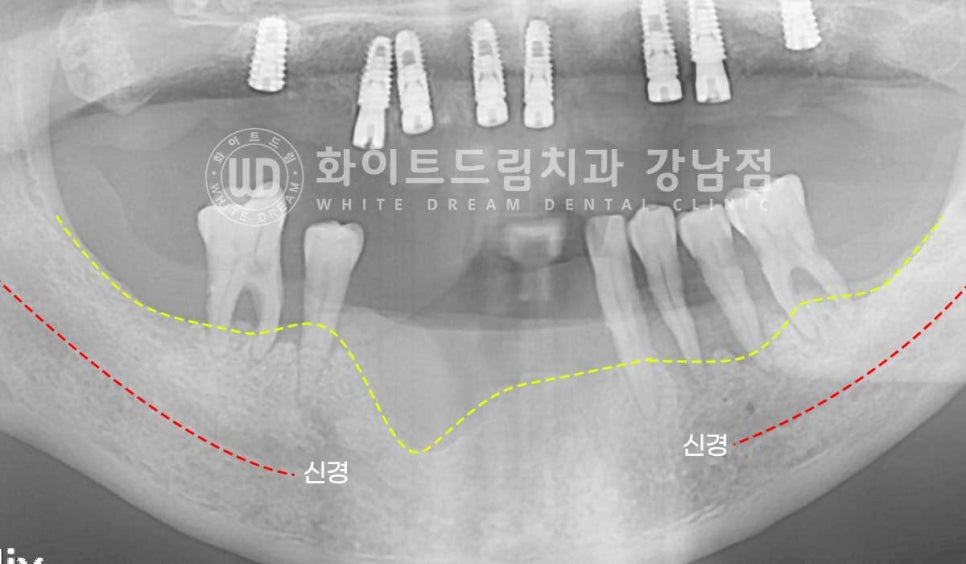

하악은 하치조 신경관이라는 구조물을 무조건 피해서 식립해야 하기 때문에

신경관 위쪽으로 10mm 이상의 잇몸뼈가 있어야 일반적인 길이의 임플란트를 식립할 수 있습니다.

환자분처럼 신경관 위쪽으로 남은 잇몸뼈의 길이가 10mm 이내일 경우에는

조금 짧은 임플란트를 선택하여 식립하게 됩니다.